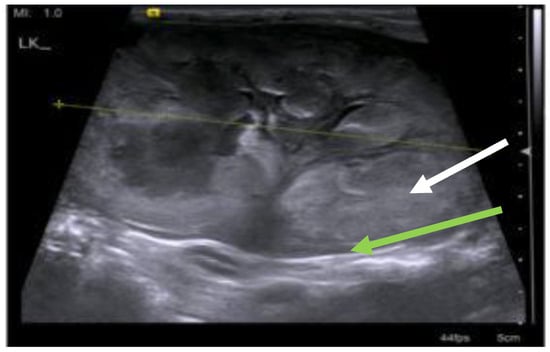

7.4. Diagnostic Imaging in FIP

7.4.1. Routine Imaging: Ultrasonographic and Radiographic Findings

| Summary of Section 7: Diagnosis of FIP; Section 7.4: Diagnostic imaging in FIP: No specific ultrasonographic or radiographic findings exist for FIP. Ultrasonography (in particular) and radiography can show the presence of effusions. Pneumonia due to FIP that is occasionally reported can be associated with radiographic changes. Ultrasonography can reveal abdominal lymphadenomegaly or lymphadenopathy and/or abnormalities of the liver, spleen, intestines and/or kidneys (which can include a medullary rim sign), depending on which organs are affected. Imaging can also be of use to the direct sampling of abnormal tissues, e.g., fine-needle aspirate for cytology examination to reveal non-septic pyogranulomatous inflammation, or ultrasound-guided needle core (e.g., tru-cut) biopsies can be collected and submitted for histopathology. When a cat is showing neurological signs, the imaging of the brain by magnetic resonance imaging, if available, with contrast, can be useful to demonstrate neurological abnormalities (such as obstructive hydrocephalus, syringomyelia, foramen magnum herniation and marked contrast enhancement of the meninges, third ventricle, mesencephalic aqueduct, and brainstem). A description of computerised tomography findings in cats with neurological FIP has not been published, but MRI is likely to be more sensitive in the detection of subtle intraparenchymal lesions. Advanced imaging of the central nervous system is indicated before performing cerebrospinal fluid sampling to assess the potential risk of herniation. |